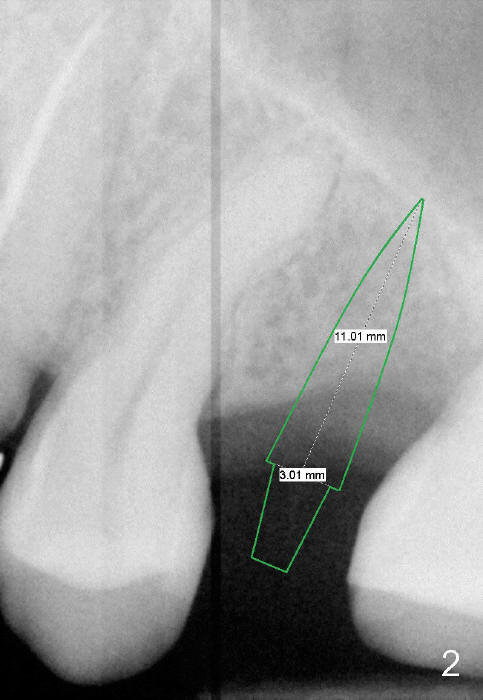

PA in Fig.1 is taken 8 months after exfoliation of the previous implant. It appears that the bone heals. One-piece implant (3x11 mm) is to be placed following tissue punch (Fig.2 green). If insertion torque is high, an immediate provisional will be fabricated (Fig.3 red). Once the implant osteointegrates, a rubber separator will be used repeatedly to move the 1st premolar mesially (arrow).